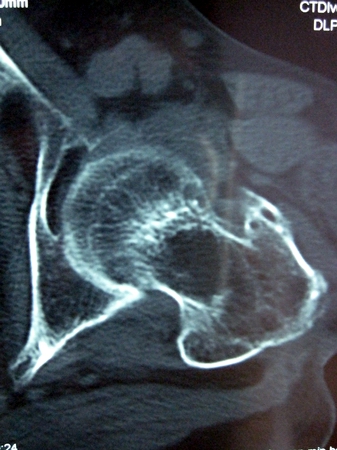

以下是引用lkc8963在2008-12-19 21:19:00的发言:[br]左?右?患侧大转子上移,股骨颈骨质浓杂,髋周见多发条片状骨化影,以小转子为著,多为陈旧性股骨颈骨折后改变并骨化性肌炎.请咨询既往史!